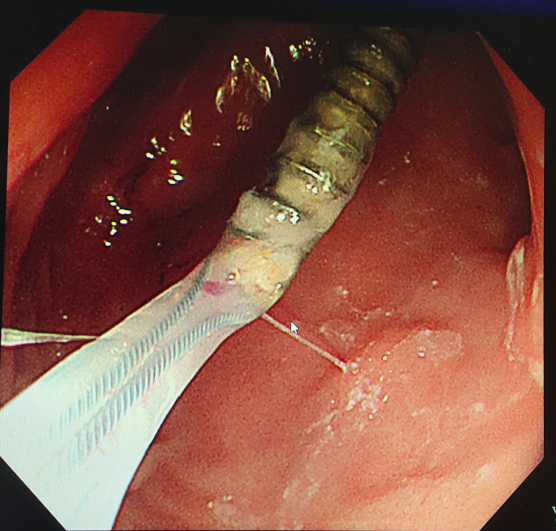

- 内镜下圈套包裹取出的螺纹钉 -

内镜下医生发现孩子的胃肠道黏膜已经有损伤、糜烂。并且随着肠道蠕动,螺丝钉现已移动到十二指肠远端。

经验丰富的李中跃主任,当即决定用圈套圈住螺纹钉近端后取出。

经过及时处理,坤坤术后第二天便能正常进食。